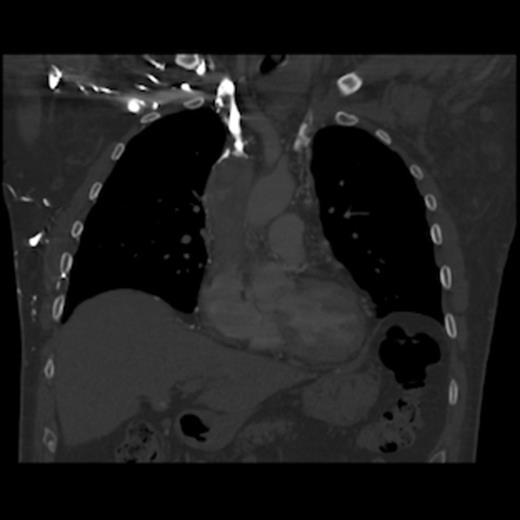

A 67-year old gentleman presented with progressive head and neck swelling and discomfort for several months. His symptoms were pronounced by bending over or straining in the bathroom. His symptoms worsened and he was referred for thoracic surgery consultation after a mass was seen on chest x-ray. He was diagnosed with SVC syndrome secondary to a mediastinal mass, demonstrated best by computed tomography (CT) [Figures 1, 2, 3].

CT of the chest (coronal section) with intravenous contrast: demonstrates complete obstruction of the superior vena cava by a large intramural thrombus that extends into brachiocephalic vein